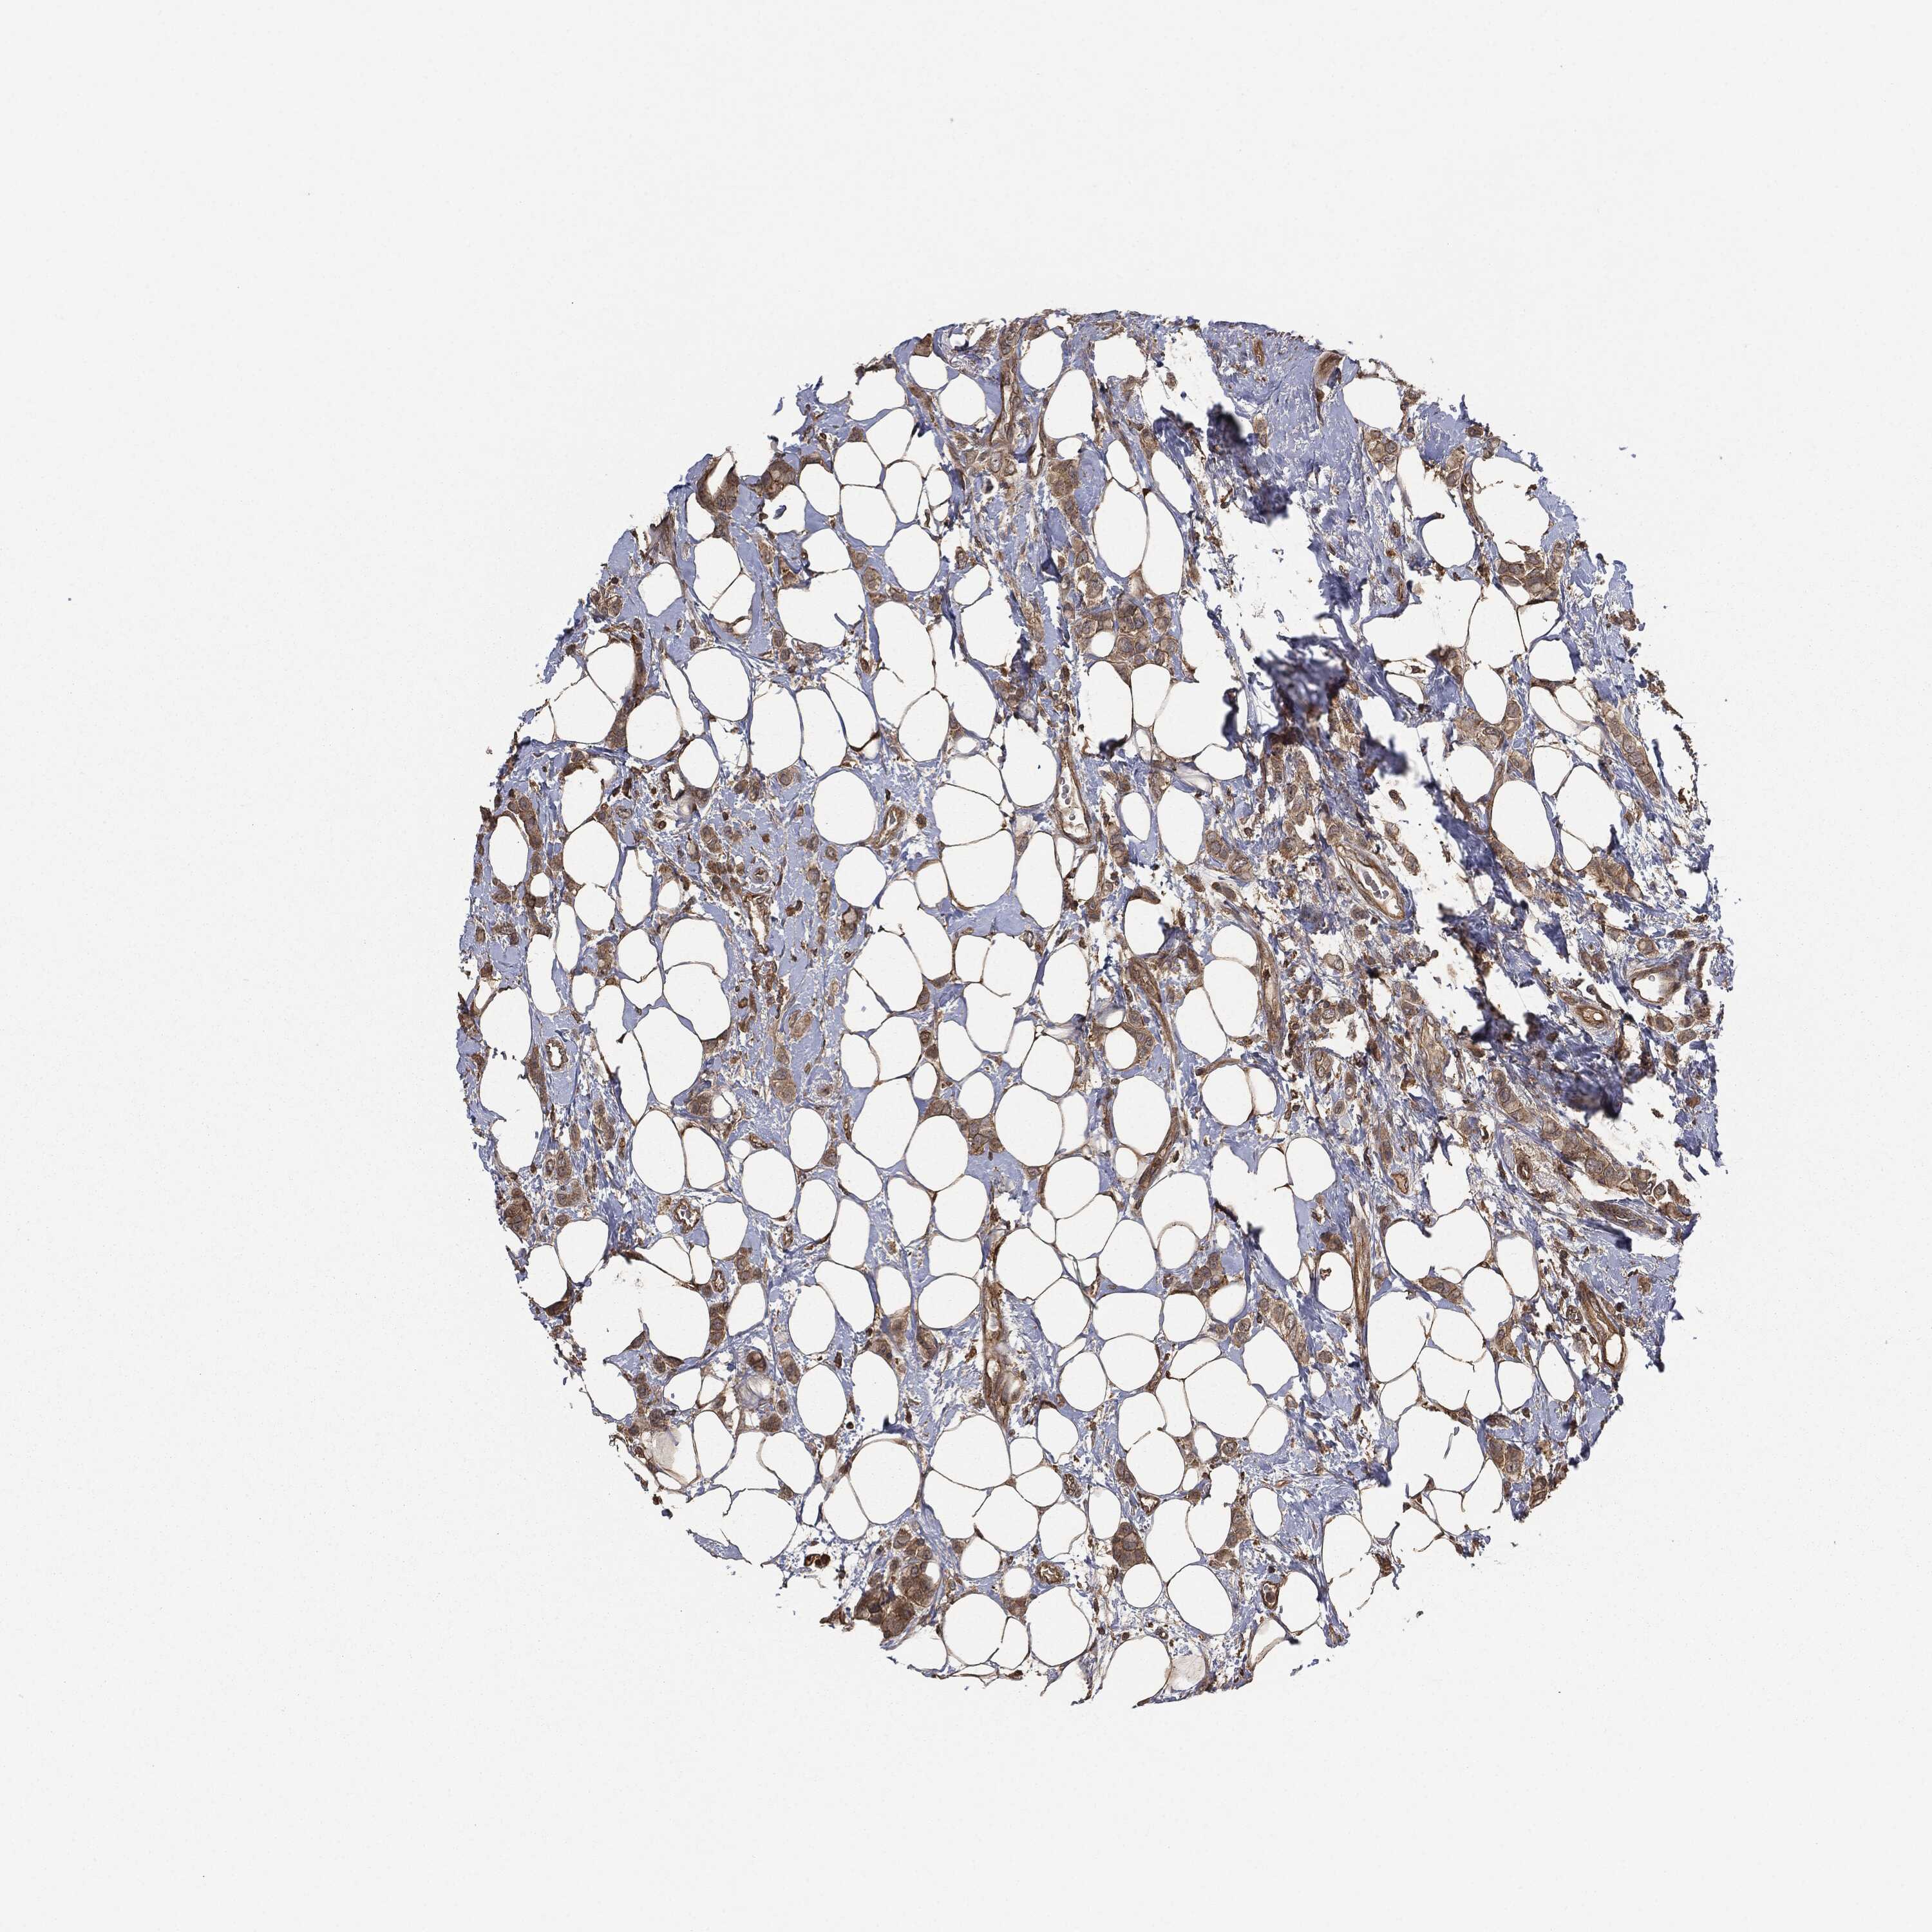

CANCER BREAST CANCER Show tissue menu

BRCA TCGA BRCA VALIDATION PROTEIN EXPRESSION